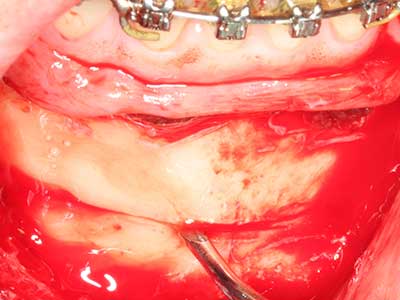

Пиезохирургията има допълнителни предимства при събиране на костни блокове. В допълнение към високата прецизност при остеотомията, описана по-горе, употребата на фините режещи накрайници значително намаляват загубата на материал. Голяма загуба на материал по време на събиране може да се очаква с дебелите накрайници, особено при употреба на борери Линдеман (Lakshmiganthan, Gokulanathan et al. 2012). Базалното разделяне, което е необходимо, особено за присадка на блок при ретромолар, е улеснено от специално създадени правоъгълни триони. В резултат на това, пиезохирургията е разглеждана като прецизна, улеснена и безопасна процедура за събиране на костни блокове в ретромоларното пространство (Happe 2007) (Фиг. 1-12).